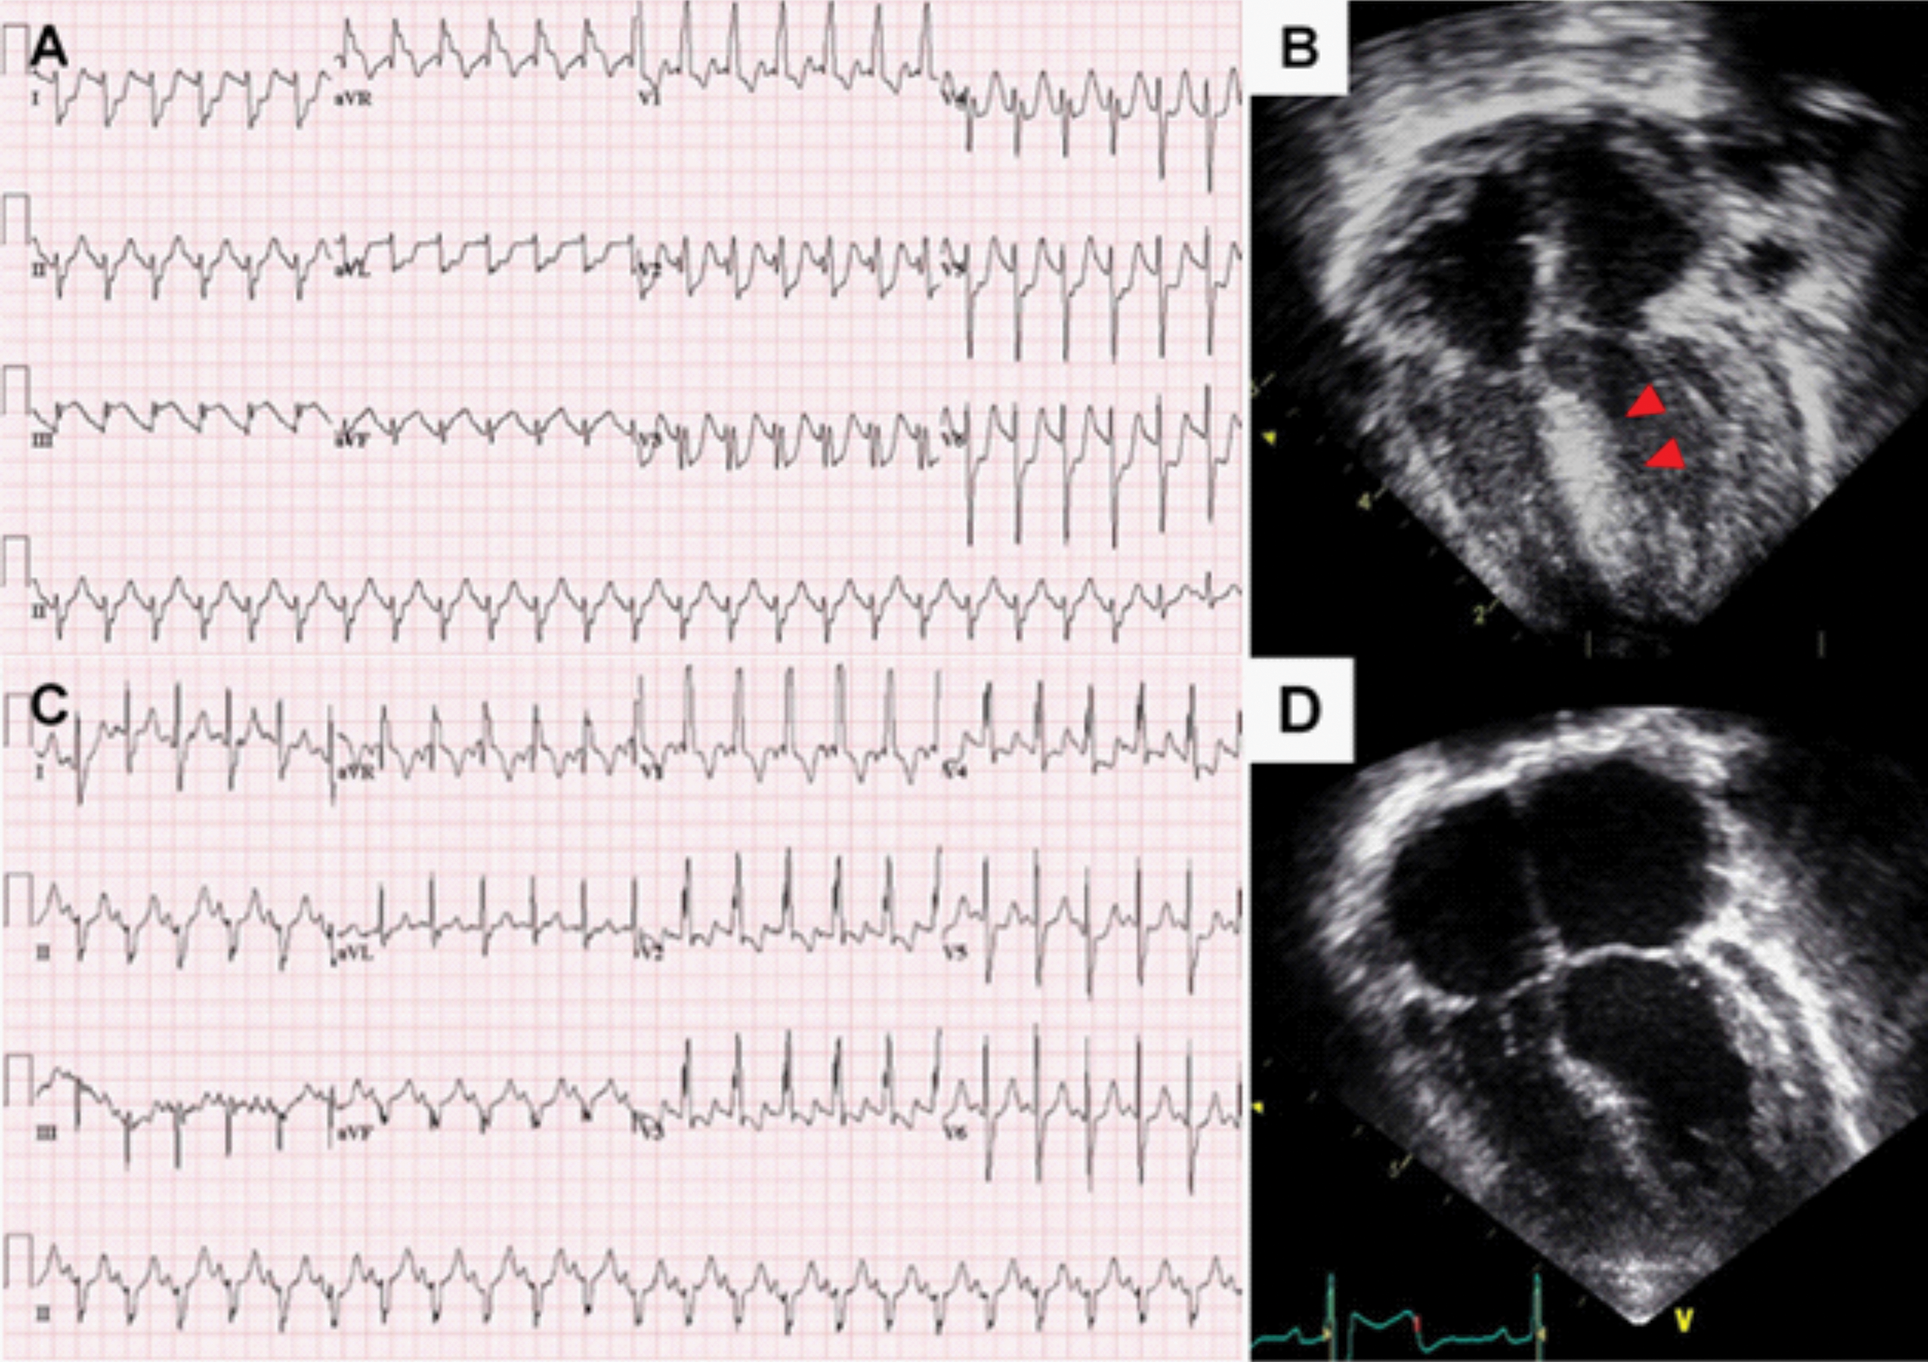

Another infant (patient 3), who underwent Rastelli operation for truncus arteriosus at the age of 14 days, experienced cardiac arrest two months after the surgery. An ECG before the arrest showed ST depressions on lead V1–6 and ST elevations in lead III and aVF (Fig. 2A). Echocardiography showed progressing LV outflow tract obstruction (peak pressure gradient; 85 mmHg), LV dysfunction (EF 40%), and increased myocardial echogenicity of the interventricular septum (Fig. 2B). She underwent LV outflow tract obstruction relief surgery and unroofing of intramural course of the LAD, which was discovered in the operating room. After the surgery, ST changes normalised and LV dysfunction improved (Figs. 2C and 2D).

Figure 2: Acute coronary event in patient 3 who underwent Rastelli procedure for truncus arteriosus

Note: (A) Electrocardiogram before cardiac arrest showed ST depressions on lead V1–6 and ST elevations in lead III and aVF. (B) Echocardiography after cardiac arrest showed increased septal echogenicity due to myocardial ischemia. (C) After unroofing of intramural course of left coronary artery, ST changes were normalised. (D) Before discharge, echocardiography showed normalized interventricular septal wall echogenicity.